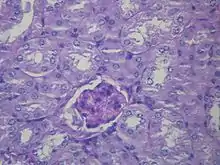

Liver histology is altered in HRS while kidney histology is normal. The upper image is a trichrome stain (chicken wire appearance) cirrhosis of the liver, the most common cause of HRS. The lower image is a PAS stain of normal kidney histology. | |